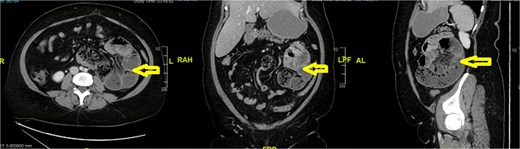

Imaging

Computed tomography (CT) abdomen revealed a left-sided paraduodenal hernia (Landzert’s fossa) with herniated small bowel loops (Fig. 1). The CT scan demonstrated a classic configuration of a left paraduodenal hernia involving Landzert’s fossa. Axial images showed a tightly packed cluster of jejunal loops located in the left upper quadrant, positioned posterior to the stomach and lateral to the fourth portion of the duodenum. The inferior mesenteric vein (IMV) and left colic artery formed the medial boundary of the hernia neck, which is a key diagnostic feature distinguishing left paraduodenal hernia from other internal hernias. The mesenteric vessels within the cluster appeared crowded and stretched, converging toward the hernia orifice—an indirect sign of mass effect within the sac. No bowel wall thickening or pneumatosis was identified. The normal C-shaped duodenum was displaced slightly medially due to pressure exerted by the herniated jejunal loops.